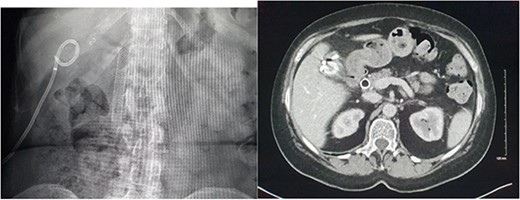

She presented on this occasion with right upper quadrant pain and collapse. Computed tomography (CT) abdomen and pelvis with intravenous contrast in the portal venous phase was performed, demonstrating perforated acute calculous cholecystitis and active haemorrhage (Fig. 1). At this point, Interventional Radiology and Upper gastrointestinal (GI) Surgery in our institution were contacted, and the patient was transferred for emergency embolization. The patient was haemodynamically unstable, so the massive transfusion protocol was commenced.

CT abdomen and pelvis with intravenous contrast in the portal venous phase was performed demonstrating perforated acute calculous cholecystitis and active haemorrhage.